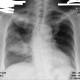

Alo dokter izin berdikusi, pasien wanita usia 57 tahun dengan keluhan batuk lama disertai nyeri dada kanan, ada riwayat penurunan berat badan. Pasien meminta second opinion karena ragu terhadap diagnosis dokter, dari dokter ada yang mengatakan bahwa diagnosis pasien lebih ke arah TB namun dari rontgen pasien juga dapat di diagnosis banding ke arah tumor. Izin dokter pada pasien, pemeriksaan lanjutan apa yang tepat untuk menegakkan diagnosis pasti?

Dan dari rontgen terlampir, pasien ini lebih cenderung ke TB atau bukan ya dok? Terimakasih dokter